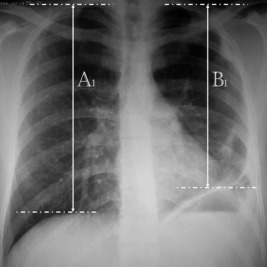

In the postoperative period, measurement was made using the same formula according to the last position of the plicated hemidiaphragm. The difference between postoperative and preoperative values was calculated, and the contribution of the plication operation on the diaphragm level was calculated (Figure 2).

Postoperative chest X-ray.

Example:

A1 = 25 cm, B1 = 22 cm

Diaphragm eventration difference in preoperative and postoperative period: 8%.